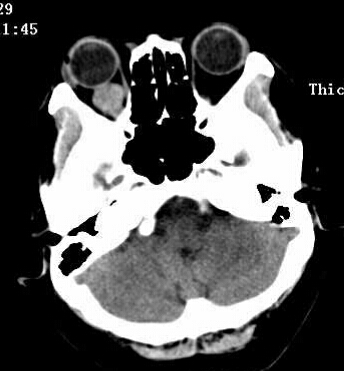

zxj320 3530天前或圆形肿块;同时累及眶内段、管内段及颅内段可表现为“哑铃形。

zxj320 3565天前及视交叉后,右眼出现典型的颞侧偏盲,从而促使患者前来就诊。

zxj320 3577天前显示病变区呈半圆形或扁平形。常合并邻近眼外肌增厚或眼环增厚。